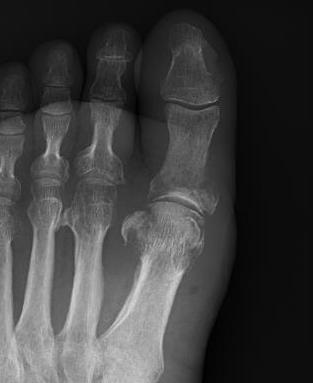

Charcot arthropathy

Midfoot ulcer with evidence of underlying Charcot arthropathy and midfoot collapse

www.boneschool.com/charcot-foot